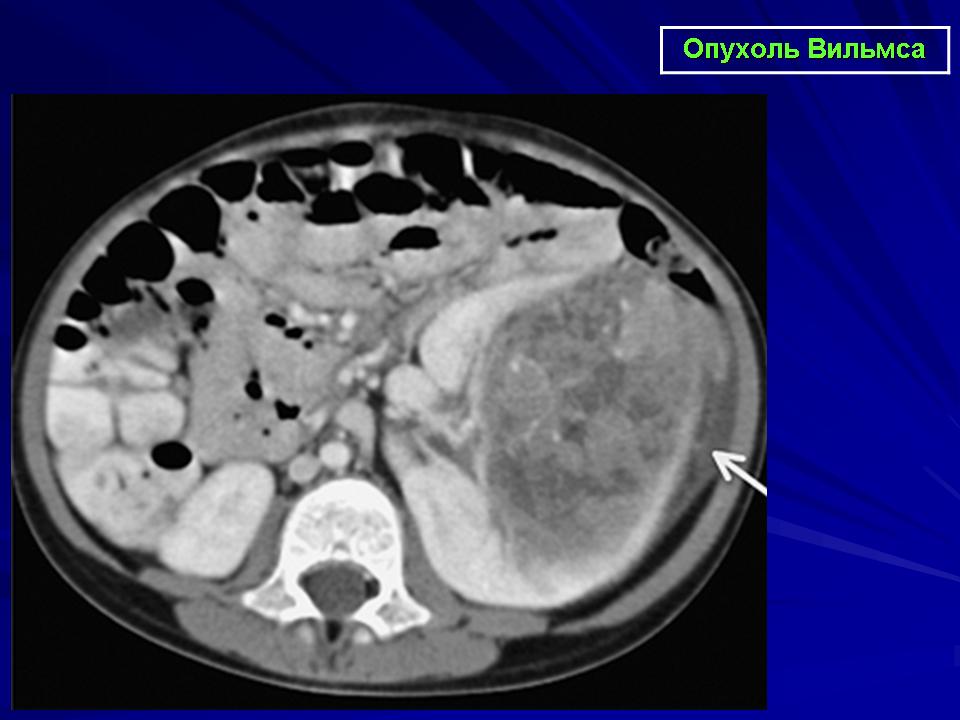

Рак в почках локализируется в левой или правой почке, возможно сразу в обеих. В самой почке рак развивается в паренхиме или в лоханке почки. Рак в почках образуется чаще всего в паренхиме почек. К ним относится: почечно-клеточный рак, Опухоль Вильмса, саркома.

Опухоль Вильмса — это нефробластома(nefro — почка, bl –ma – опухоль), которая встречается у 7 детей из 1 миллиона по всему миру, в возрасте до 5 лет. Встречается среди девочек и мальчиков одинаково. Из-за генетической мутации происходит ненормальный агрессивный рост клеток в паренхиме почки. Ее можно вылечить в 90% случаев.

Лучевая терапия как вариант лечения рака почки очень редко. Опухоль не чувствительна к облучению. Облучение используют для облегчения болей при метастазировании в кости и головной мозг. Стоит отметить, что облучение хорошо влияет на опухоль Вильмса у детей, но радиоактивное излучение имеет плохие последствия в развитии ребенка.